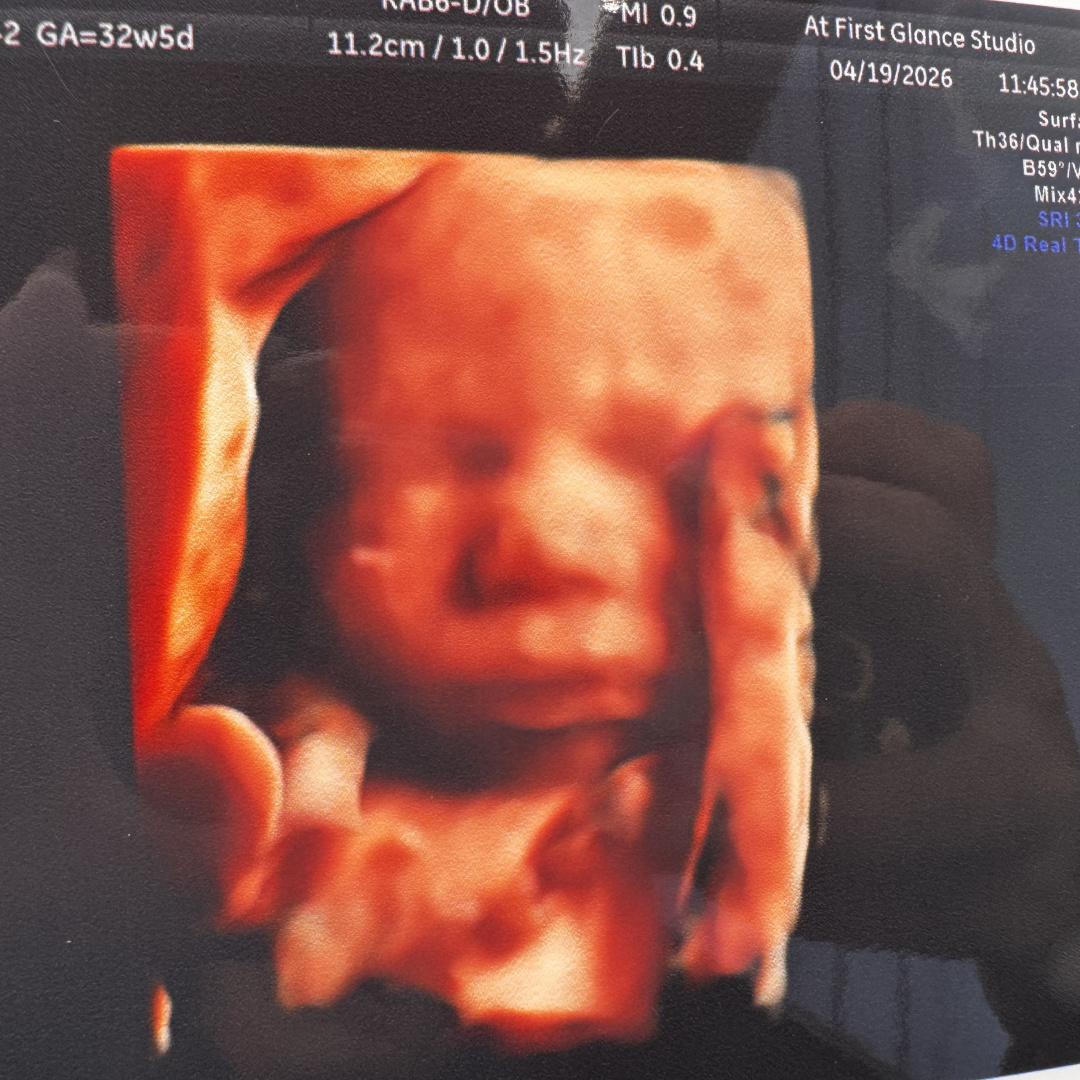

Ali Nour Chaaban❤️